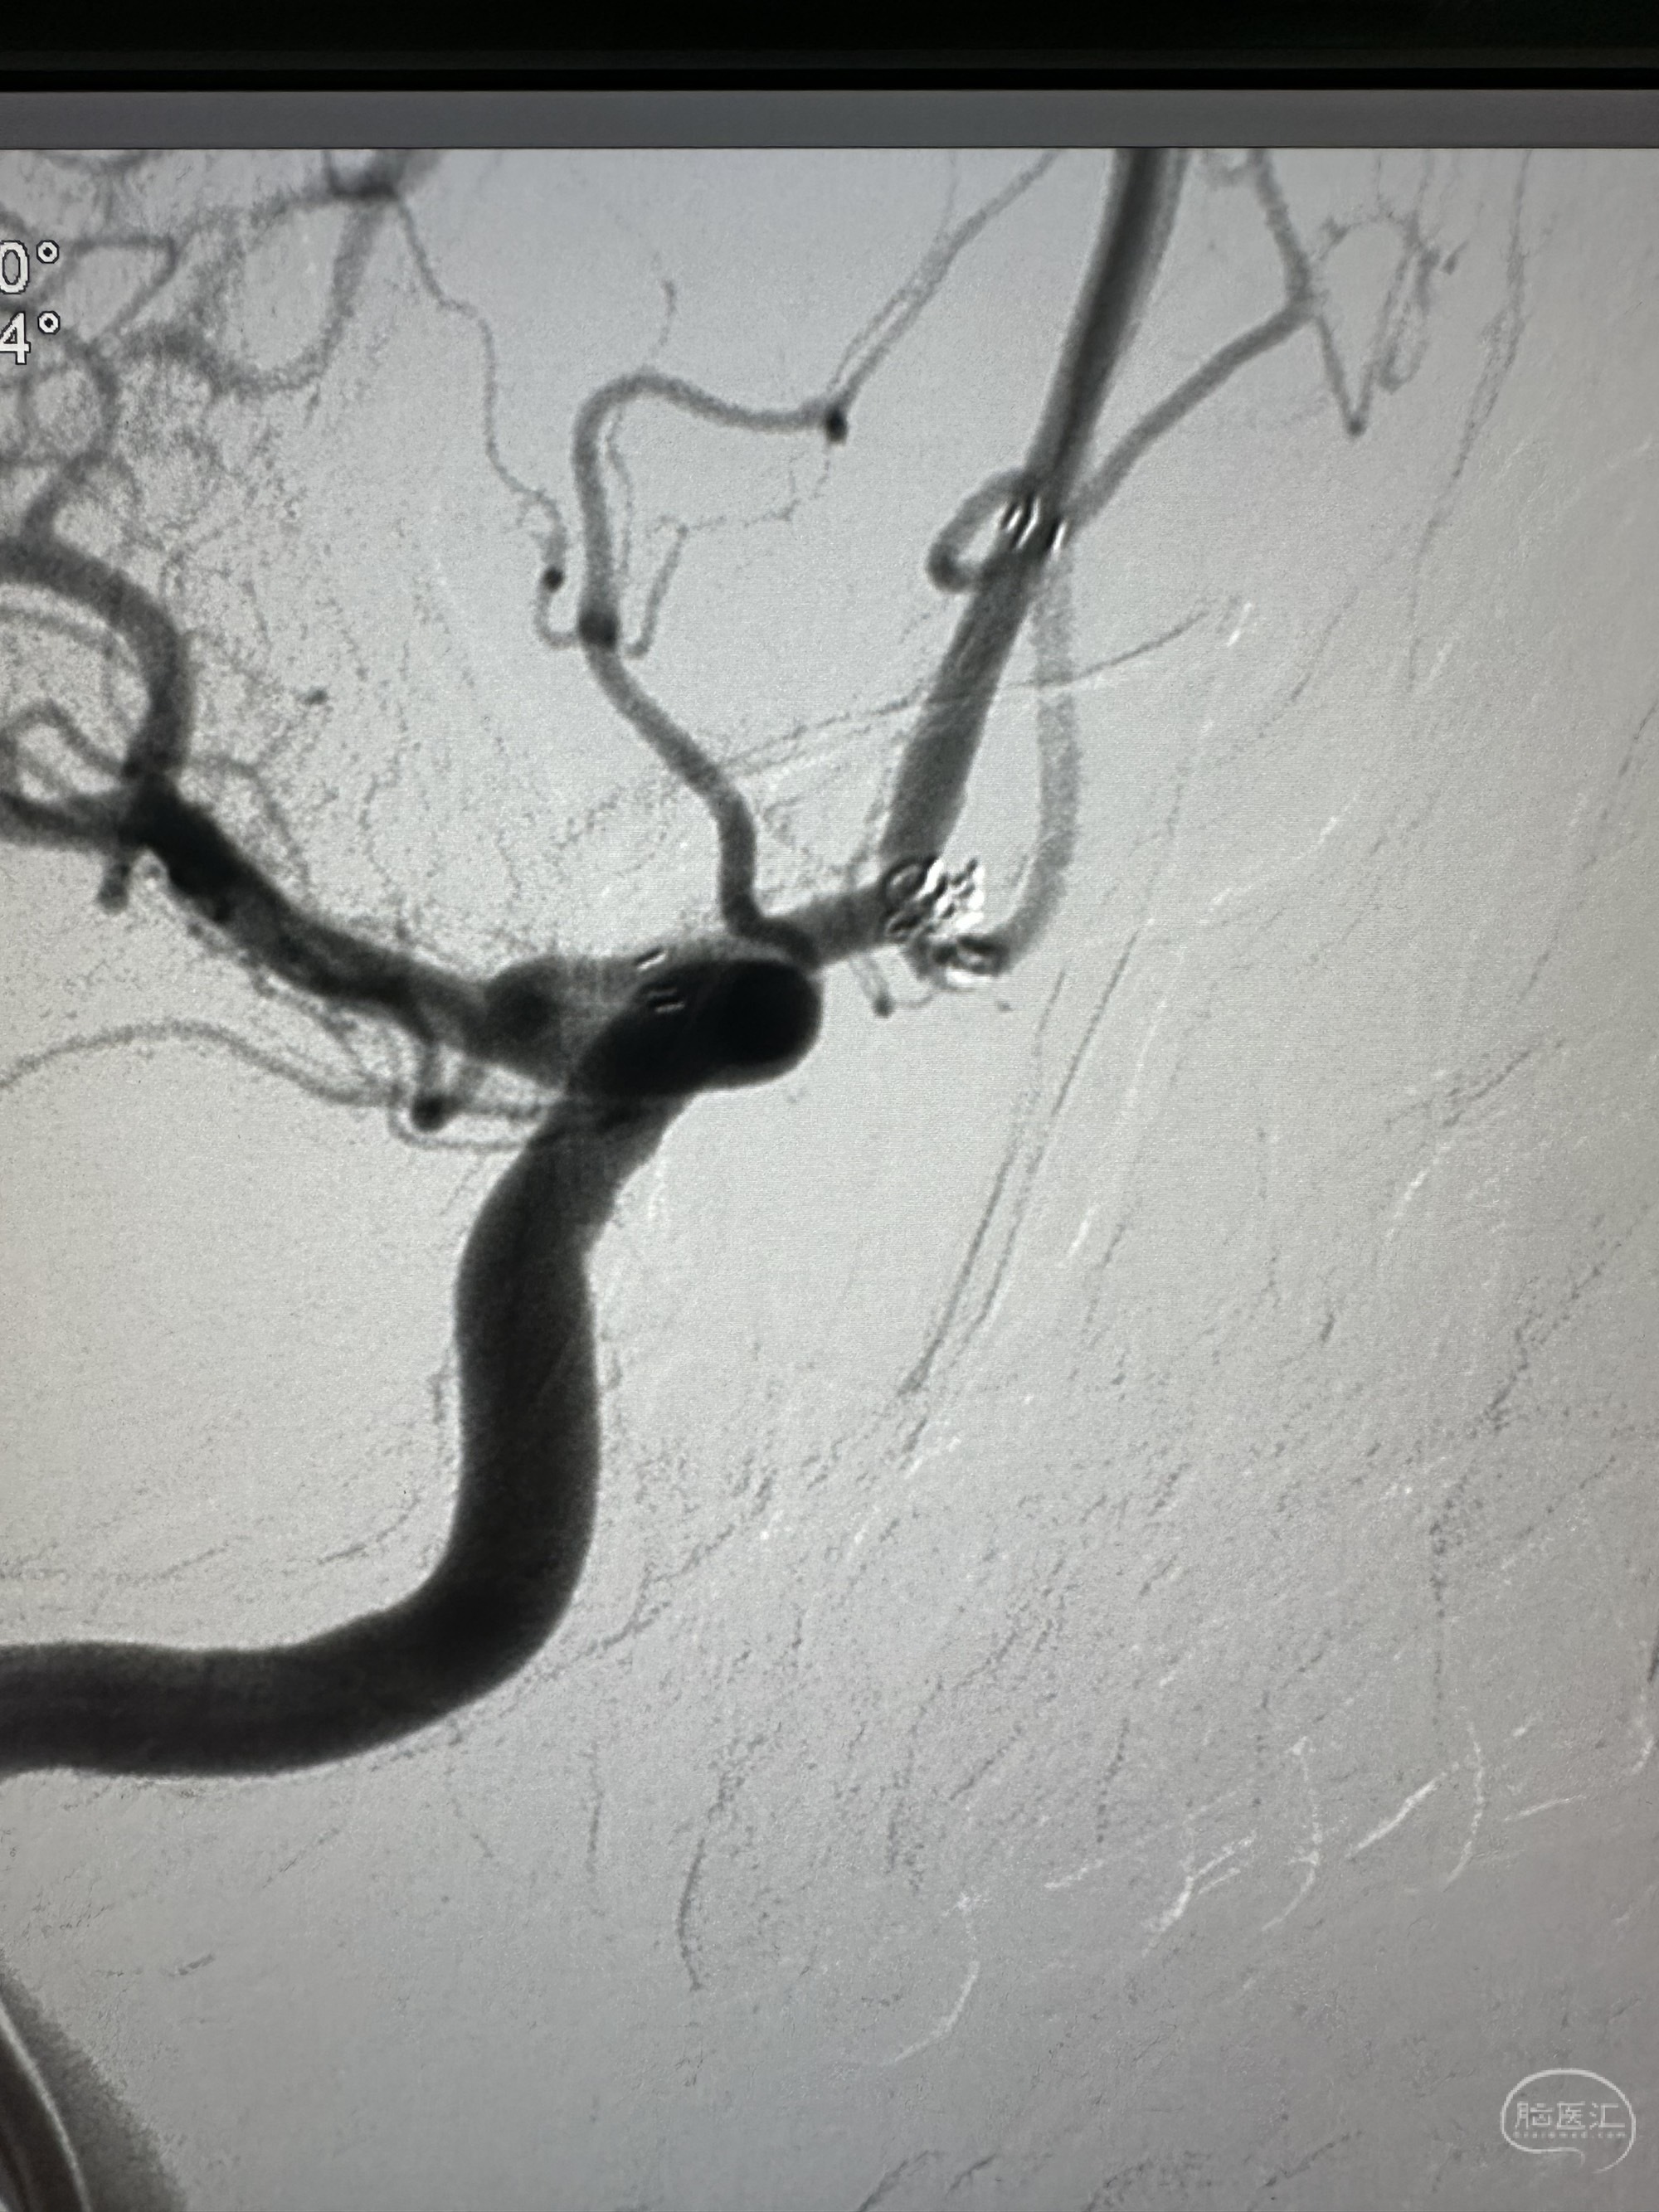

最后正位

侧位